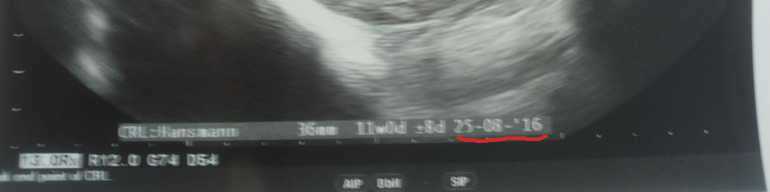

Результаты: УЗИ, КТГ, доплера, скринингаВот и наступил этот день, самый волнительный для меня, прошла первый скрининг) срок поставили 12 недель и 3 дня, с моими подсчётами разница в 1 день. Врач попалась не в настроении, разговаривала сквозь зубы, ну и на этом есть большое человеческое спасибо, что вообще разговаривала со мной и сказала самое главное для меня "узи хорошее, кровь отличная"😍ПДР совпало с подсчётами гини 28.08.2016)))) тонуса нет, ребёночек хулиган, будет либо каратистом либо футболистом)))) я счастлива, что ещё сказать))))а забыла, пол узнать даже предположительно не удалось, т.к. между ножками пуповина. Заранее прошу прошения за орфографические и пунктуационные ошибки, пишу с телефона сидя в такси)))

И я Вас поздравляю)))) у нас ктр 64 мм, а у меня ПДР в результат написано было) и утр у Вас будет, если не секрет?)😀

Адя ,а вам фотки с узи не дали? У меня на узи прям на фотке снизу ПДР написанно, сама программа высчитывает.